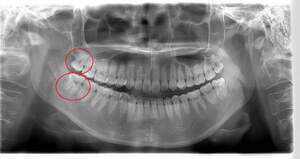

- 抜歯前写真(レントゲン)

| 親知らずの生え方 | 完全に埋まっている、横向きに生えている |

| 抜歯内容 | 左下親知らずが横向きになって半分埋まっている状態だったため、麻酔を行い、親知らずの奥の歯ぐきに切開をいれ、歯が囲んでいる骨を削り、歯の頭の部分を削って出し、その後根の部分に器具をかけて抜歯しました。 親知らずが一部神経に近い部分があったため、術後に麻痺が出る可能性がありました。このケースでは事前にCTを撮影し、歯の位置、根の方向、神経との距離を確認していたため、幸い麻痺が出ることはありませんでした。 術後1週間経過して糸取りをして治療は終了となりました。抜歯後3日間は腫れと痛みで大変だったが、糸取りをする頃には痛みも腫れも無くなったと患者さまも喜んでおられました。 |